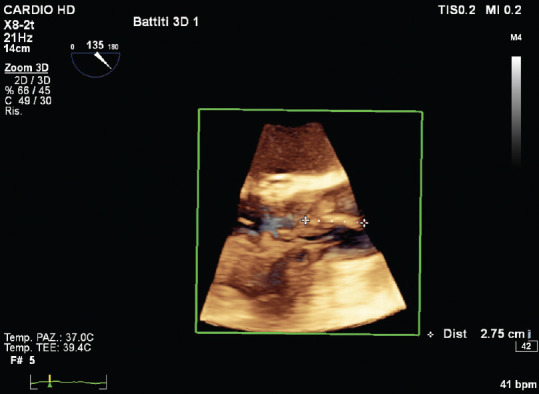

感染性心内膜炎(IE)的诊断基于临床怀疑,并辅以一致的微生物学和仪器数据。心脏瓣膜(原生瓣膜或人工瓣膜)或人工心内膜受累的证据是 IE 的主要诊断标准。经胸超声心动图(TTE)是初步诊断的首选技术,而经食道超声心动图(TEE)则推荐用于 TTE 未确诊或阴性的患者、高度怀疑 IE 的患者以及 TTE 阳性的患者,以记录局部并发症。在对无并发症的 IE 进行随访时,应考虑重复 TTE 和/或 TEE,以检测新的无声并发症并监测植被的大小。在 IE 的情况下,三维(3D)TEE 的作用越来越大;事实上,这种技术也被证明有助于诊断 IE 及其并发症,因为它可以获得无限平面和容积重建。在这篇综述中,我们将介绍三维 TEE 的实用性及其在 IE 治疗中的附加值。

Infective endocarditis (IE) diagnosis is based on a clinical suspicion supported by consistent microbiological and instrumental data. Evidence of involvement of cardiac valves (native or prosthetic) or prosthetic intracardiac material is a major diagnostic criterion of IE. Transthoracic echocardiography (TTE) is the initial technique of choice for the diagnosis while transesophageal echocardiography (TEE) is recommended in patients with an inconclusive or negative TTE, in patients with high suspicion of IE, as well as in patients with a positive TTE, in order to document local complications. Repeating TTE and/or TEE should be considered during follow-up of uncomplicated IE, in order to detect new silent complications and monitor vegetation size. In the setting of IE, the role of three-dimensional (3D) TEE is increasing; in fact, this technique has also been shown to be useful for the diagnosis of IE and its complications as it allows to obtain infinite planes and volumetric reconstructions. In this review, we will describe the usefulness of 3D-TEE and its added value in the management of IE.